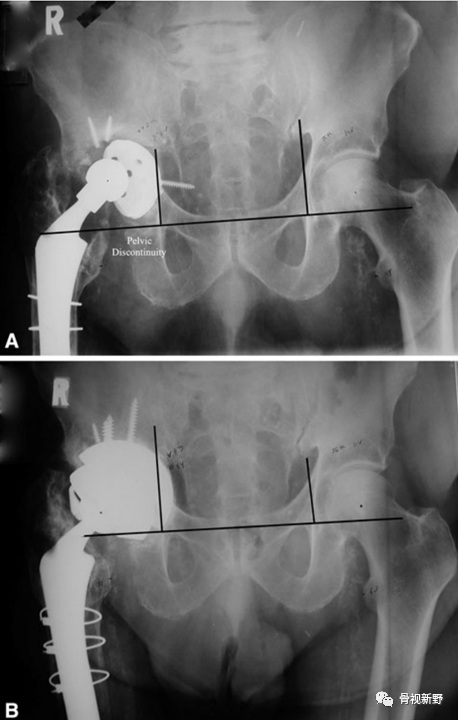

Case 1: Paprosky IIIb

男性,78岁。因右髋部骨折,于25年前行右髋THA。入院前半年开始出现右髋部疼痛、活动受限,加重1月。影像资料提示假体松动、移位;股骨侧及髋臼侧严重骨缺损(Paprosky IIIb )。

完善术前常规检查后,择期行翻修术:髋臼侧以cup-in-cup技术翻修;股骨侧以水泥柄翻修。

术后X光片